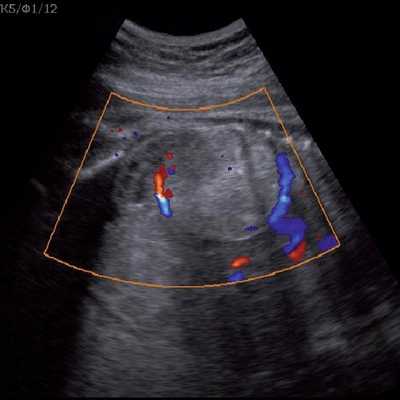

Цветовое допплеровское картирование помогает идентифицировать питающий опухоль сосуд, отходящий непосредственно от аорты, однако такой единственный сосуд может и не визуализироваться [13].

Под диафрагмой справа визуализировалось гиперэхогенное опухолевидное образование несколько неоднородной солидной структуры, с четкими ровными контурами, размером 50x38x35 мм. К нижнему полюсу данного образования прилежала правая почка, имеющая нормальные размеры, форму и структуру. Нижняя полая вена была смещена кпереди и влево. Обращала на себя внимание выраженная гепатомегалия, причем структура печени не была однородной. Она содержала множественные гиперэхогенные включения размерами до 17 мм, окруженные тонким гипоэхогенным периферическим ободком. Цветовое допплеровское картирование(ЦДК) демонстрировало интенсивную периферическую васкуляризацию опухоли (рис. 1-3).

Рис. 2. Кровоток в нейробластоме плода. Цветовое допплеровское картирование. Отчетливо виден питающий сосуд, огибающий образование по его периферии. К нижнему полюсу образования прилежит интактная почка плода.